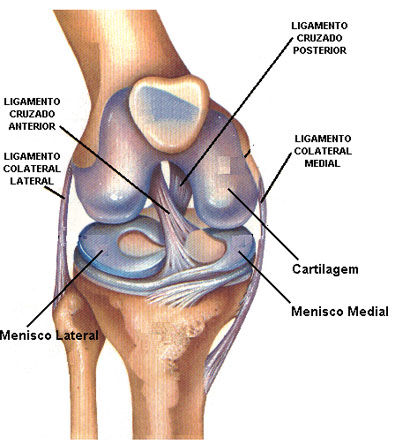

1. LCA

1. Tendón rotuliano

1. Disminuye la flexión